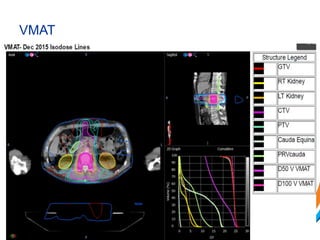

VMAT

Cyberknife